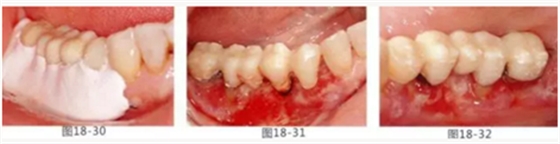

圖18-30 在頰側以及舌側涂上牙周塞治劑。然后將咬合面少許削除。

圖18-31 手術完成1周的頰側面照。

圖18-32 同部位的舌側面照。